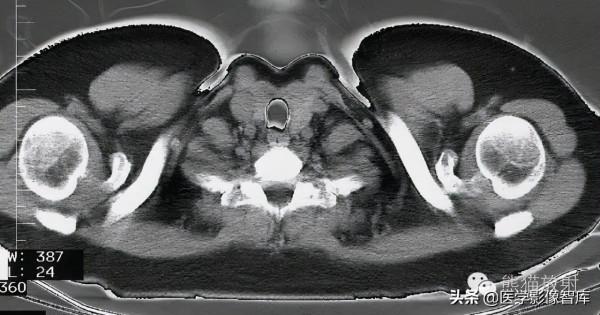

盆腔